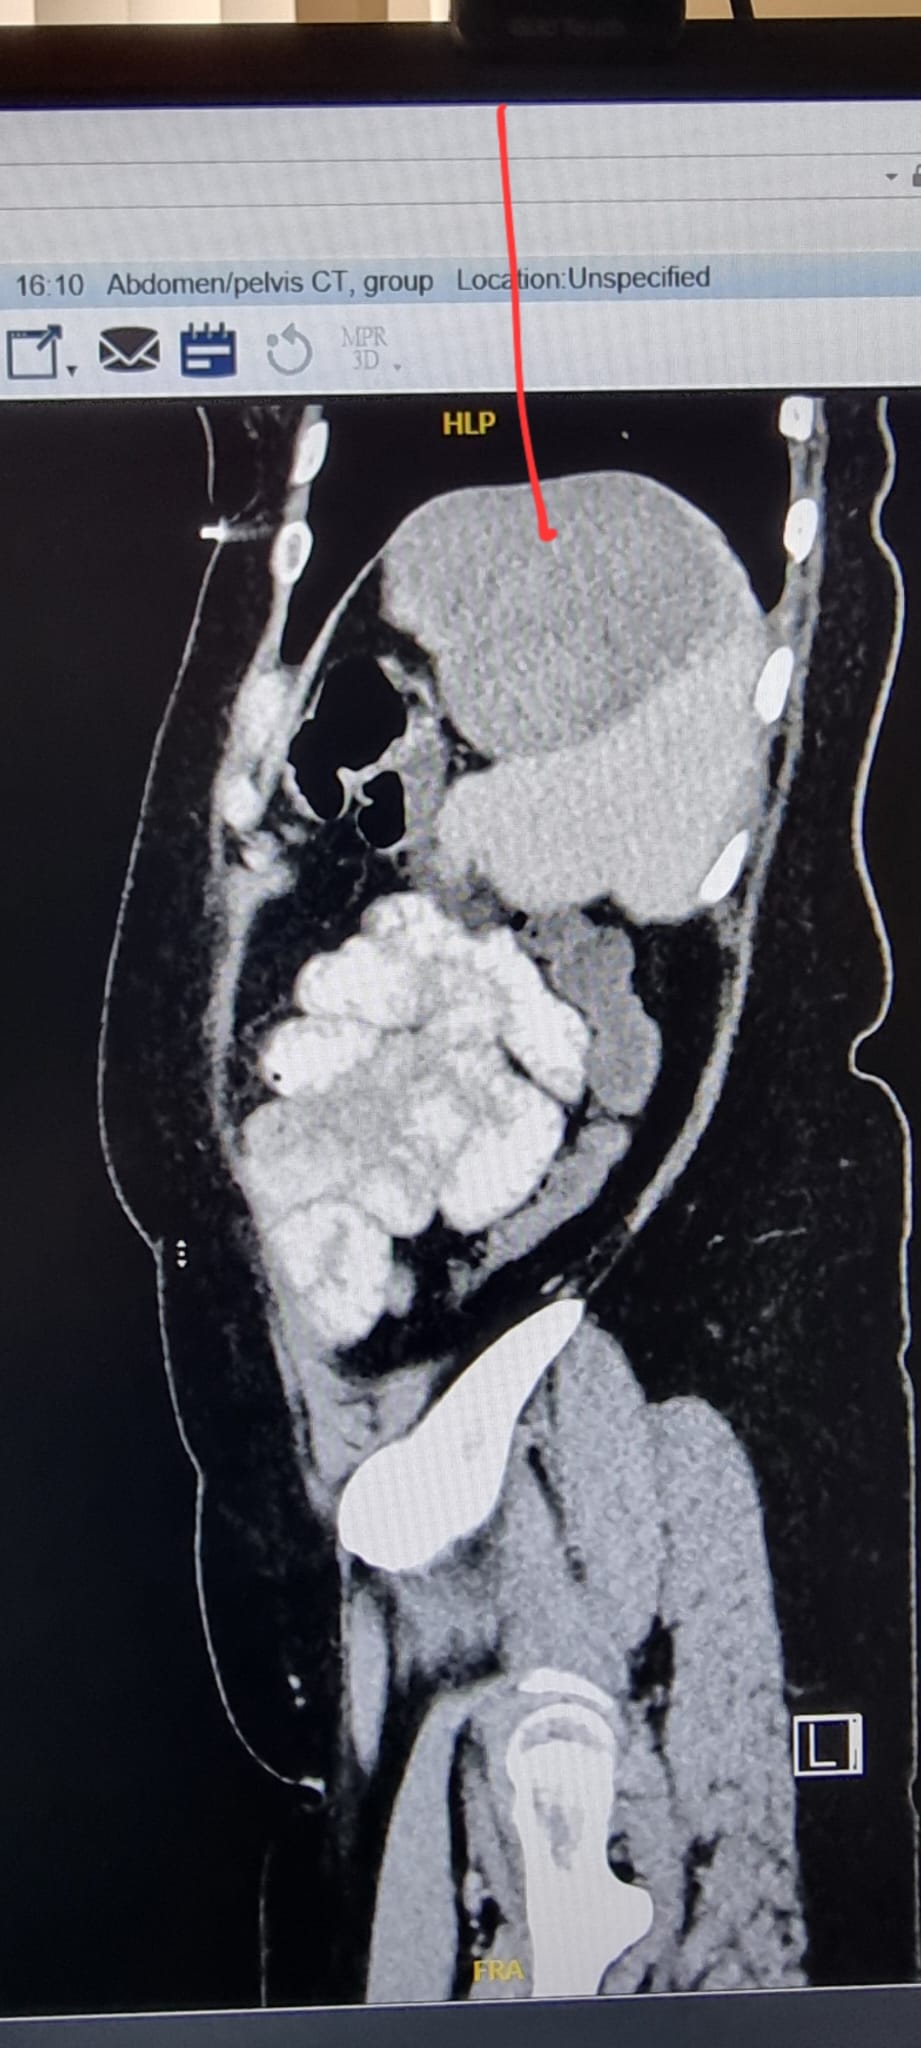

עם הגעתה למרכז הרפואי, ביצעה שירלי בדיקות שונות, ובהן: אולטרסאונד בטן וכליות, וצילומי C.T בטן ואגן, בהן התגלה באונה השמאלית של הכבד גידול שפיר, בגודל כ-11 ס"מ (!). בעקבות הממצאים, הוכנסה המטופלת לניתוח דחוף.

כך נראתה ההדמיה שבוצעה בבית החולים והציגה את הגידול הענק.